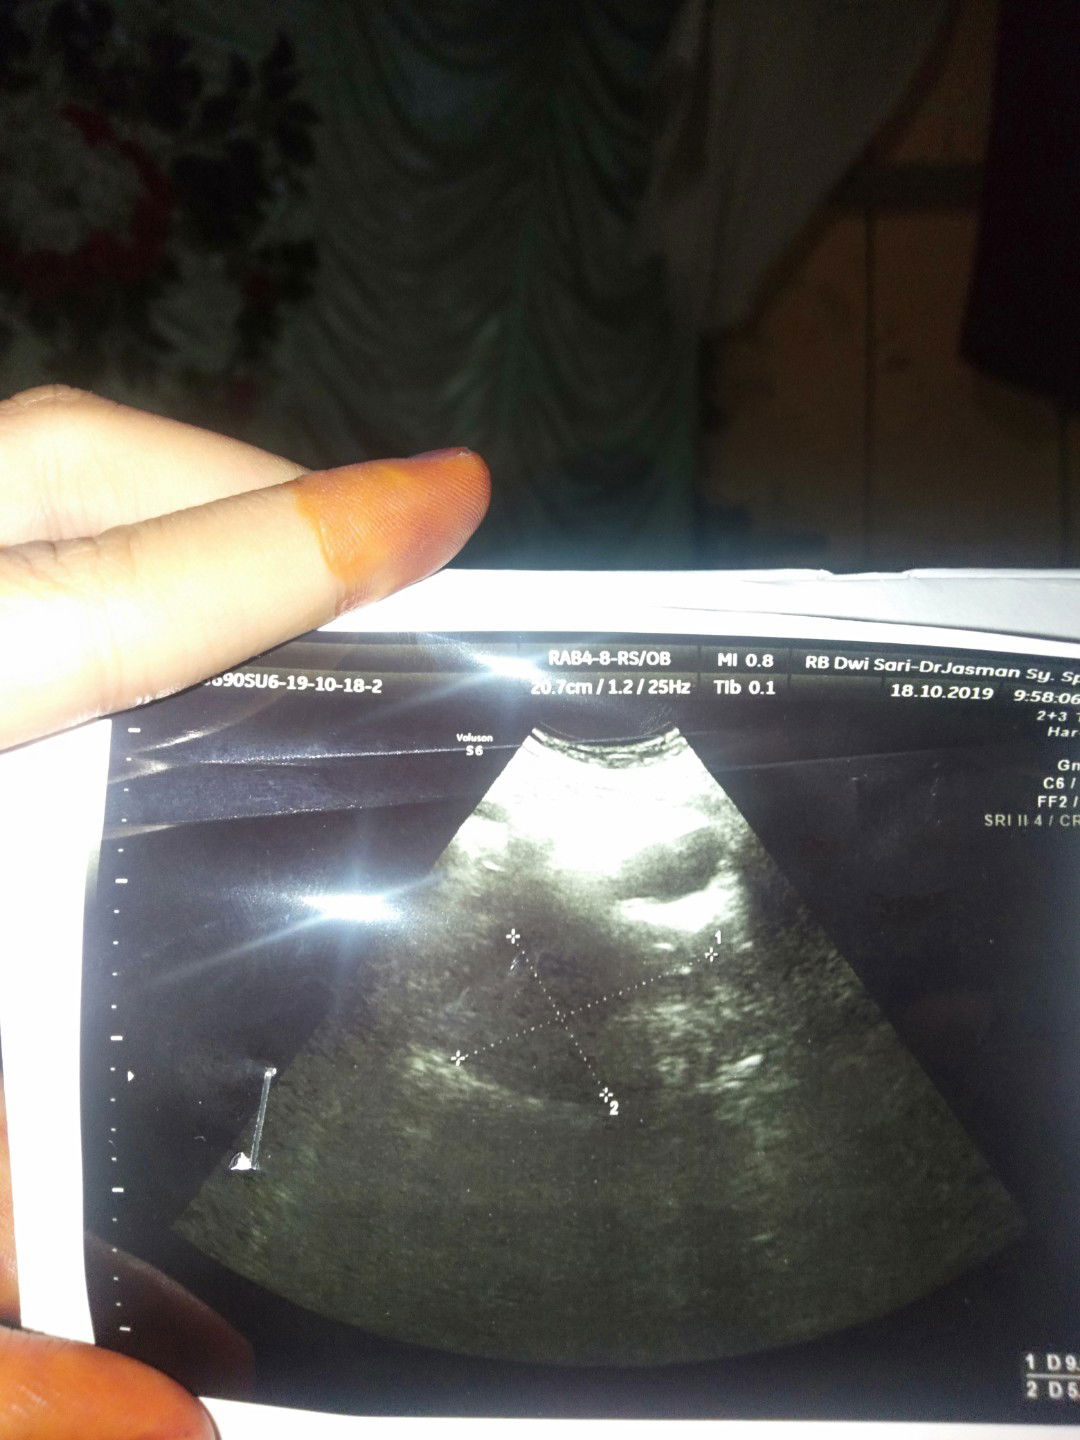

usg pasca keguguran

USG pasca keguguran kata dokter udah bersih tapi masih ada kluar ,,info donk Bun untuk bersih i rahim pakai apa,ini hasil USG saya